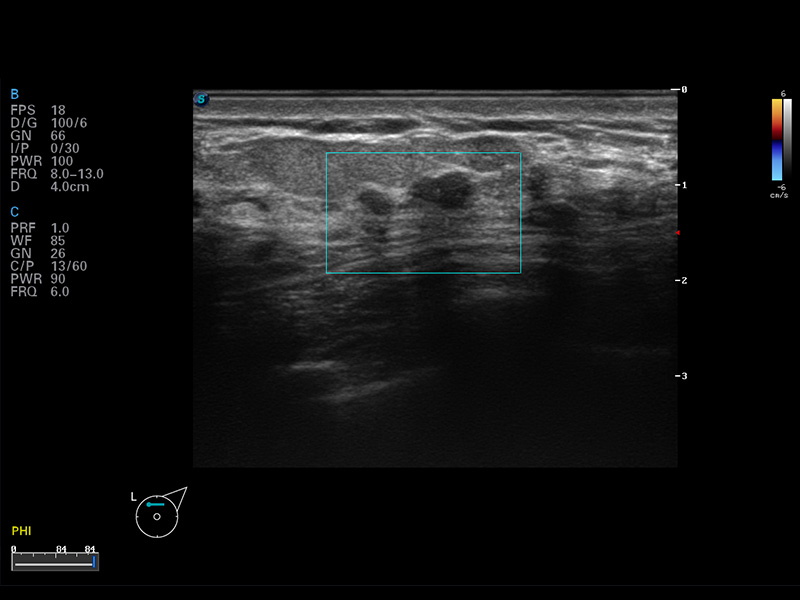

S8 EXP便携式彩色多普勒超声诊断仪是开立医疗研发的高端全身应用型便携彩超。高通道的VIS平台融合可视化(Visual)、智能化(Intelligent)和人性化(Smart)的特点,配以开立医疗自主研发生产的探头大家族,使您能够快速、准确的获得病人信息,提高工作效率的同时减轻疲劳。

成像技术

多波束形成器